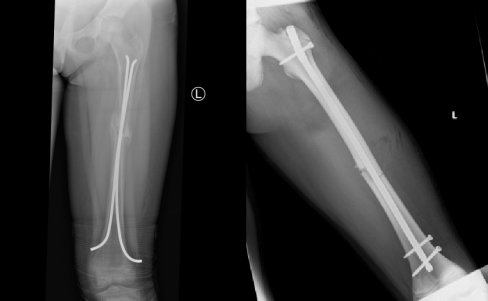

Below are guidelines to management of femur shaft fractures; however, these may vary between facilities, depending on the preference and expertise of the surgeons.

Age | Treatment | Duration | Comments |

---|---|---|---|

Neonates | Pavlik harness | 3 weeks | |

<2yr / <12kg | Gallows traction | 3–6 weeks | Compartment syndrome risk |

2–8 years | Early spica cast | 4-8 weeks | |

8–12 years | Traction | 6–8 weeks | |

Retrograde IM nails | Partially weight bearing to full as pain permits | Removal at 6 months | |

>12 years | Prograde IM nails | Trochanteric entry point. Locked nail | |

Special circumstances | |||

Compound fractures | External fixator/plate with preliminary debridement, antibiotics | ||

Severe head injury | ORIF (done once patient’s condition stabilised) |